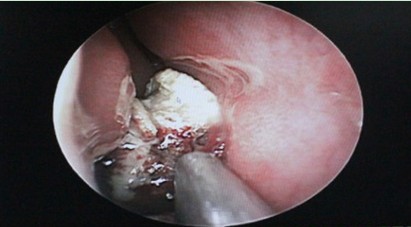

医院接诊医生详细询问了小徐的病史,并行鼻内镜检查,镜下显示:小徐的双侧鼻腔粘膜苍白,双侧下鼻甲肥大,右侧鼻道可见一个不规则型的肿物,质地坚硬,可活动,表面伪膜附着,周边粘膜炎性改变,触之易出血。鉴于患者复杂的病情,门诊医生随即建议小徐住院做进一步检查。通过对鼻窦CT及各种检查结果分析,医生的较终诊断是:小徐患有慢性鼻炎、鼻中隔偏曲、右侧筛窦、蝶窦炎,而这一切问题的发生,都与右鼻腔内这一脓肿物的存在有着千丝万缕的联系,看来需要通过手术进一步确定其性质,找出造成八年鼻疾的真正元凶。

(鼻内镜下可见小徐鼻道内不规则型肿物)

1月5日,由西安新城中大耳鼻喉医院冯亮医生主刀,经局麻、在鼻内镜下为患者行右鼻手术,术中探及这一神秘的肿块儿,发现竟是一块直径约2cm的橡皮异物,由于滞留鼻腔时间太长,橡皮表面形成的钙化结晶盐,已堵塞在下鼻道和鼻中隔之间。遂在鼻内镜下去除异物,同时又进行了右侧筛窦开放、蝶窦口扩大术,清理了蝶窦腔内囊肿,较后以明胶海绵填塞右侧鼻腔,手术顺利完成。